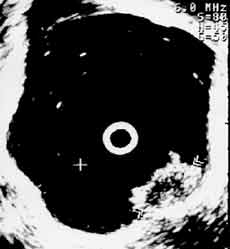

(Справа) Рак мочевого пузыря стадия Т1.